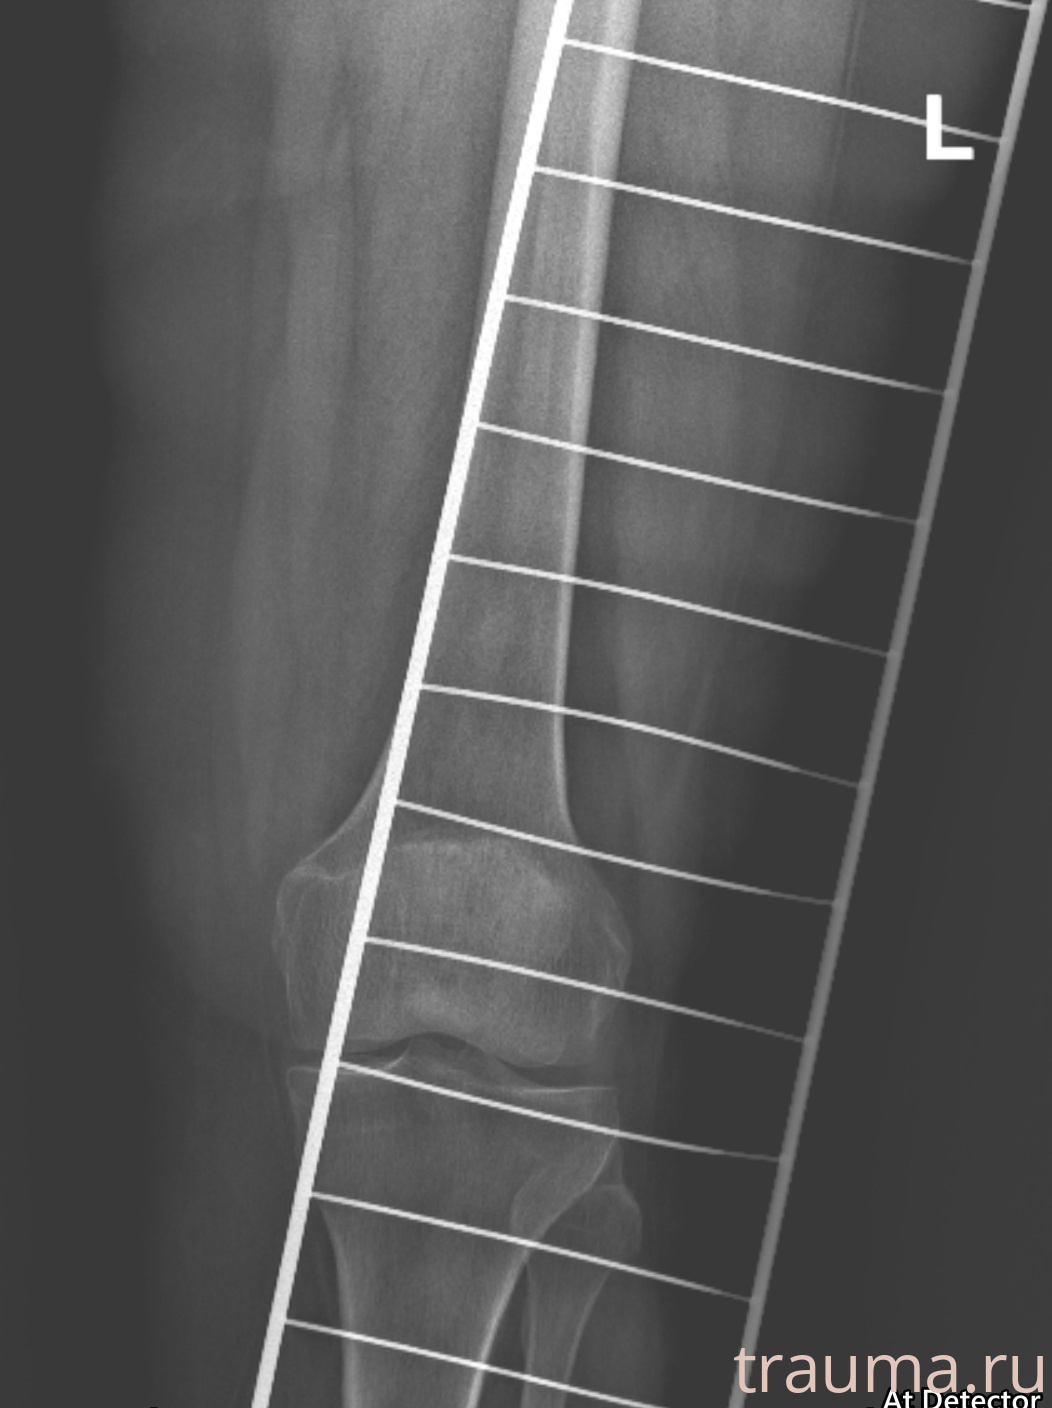

Рентген на дому: по вашему адресу приезжает врач-рентгенолог, травматолог-ортопед с мобильным рентгеновским аппаратом, проводит диагностику травмы или заболевания, делает необходимые рентгенограммы, дает рекомендации по дальнейшему лечению. Получить качественные снимки в домашних условиях возможно благодаря уникальной методике, разработанной МосРентген Центром для института  Склифосовского